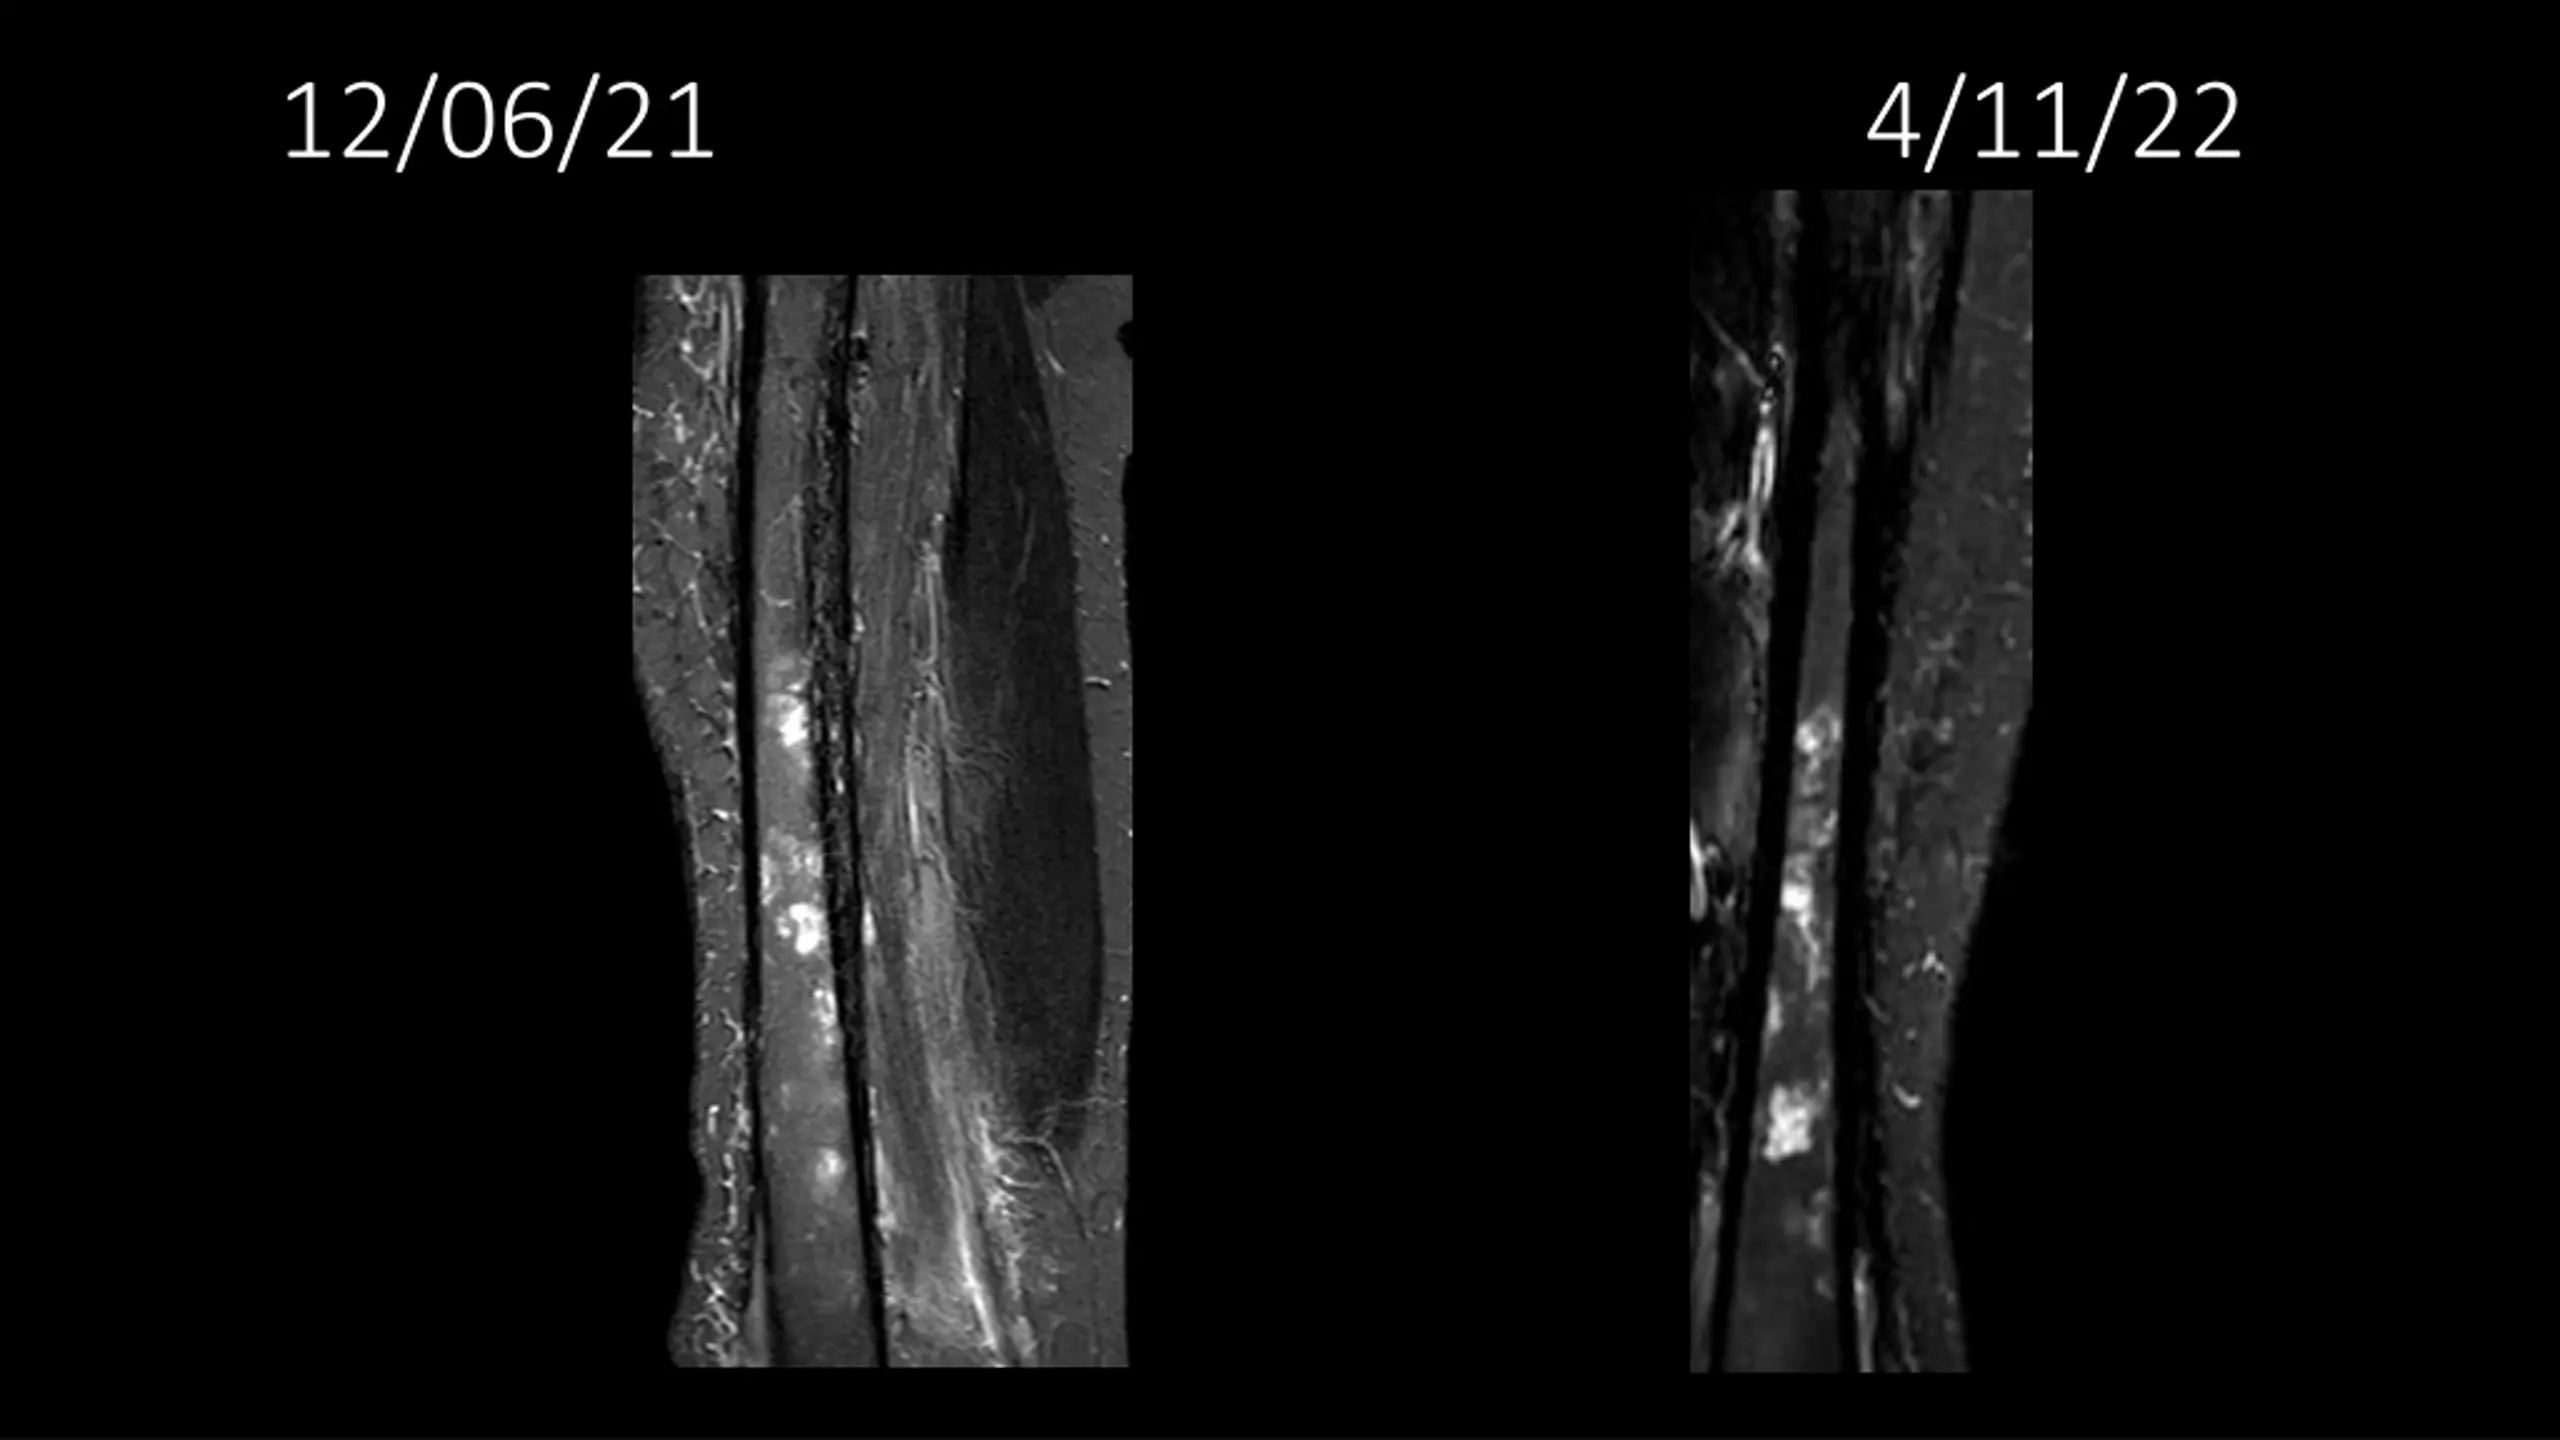

62-year-old shows post-surgery progress from 11/4/2020 to 4/11/22

Explore the journey of a 62-year-old individual post-UPS resection on 11/4/2020, through a series of dated images leading up to 4/11/22. Witness the transformation and recovery process in these visual updates reflecting the progression over time.